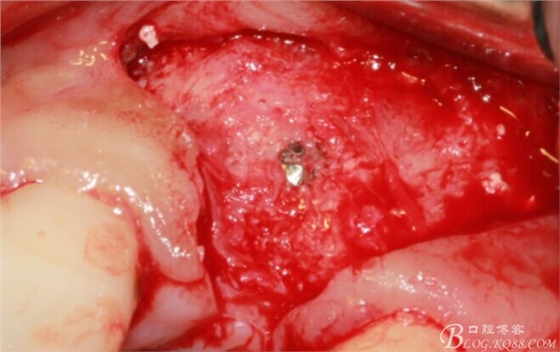

于是我果斷告知患者,手術(shù)失敗了,不能拖延,如不及時(shí)處理,炎癥繼續(xù)發(fā)展會(huì)很快波及鄰牙牙槽骨。患者接受我的建議。切開翻瓣,骨粉及生物膜消失了,骨吸收嚴(yán)重,幸運(yùn)的是,因?yàn)樘幚砑皶r(shí),鄰牙骨支持依然存在。

徹底掻刮。